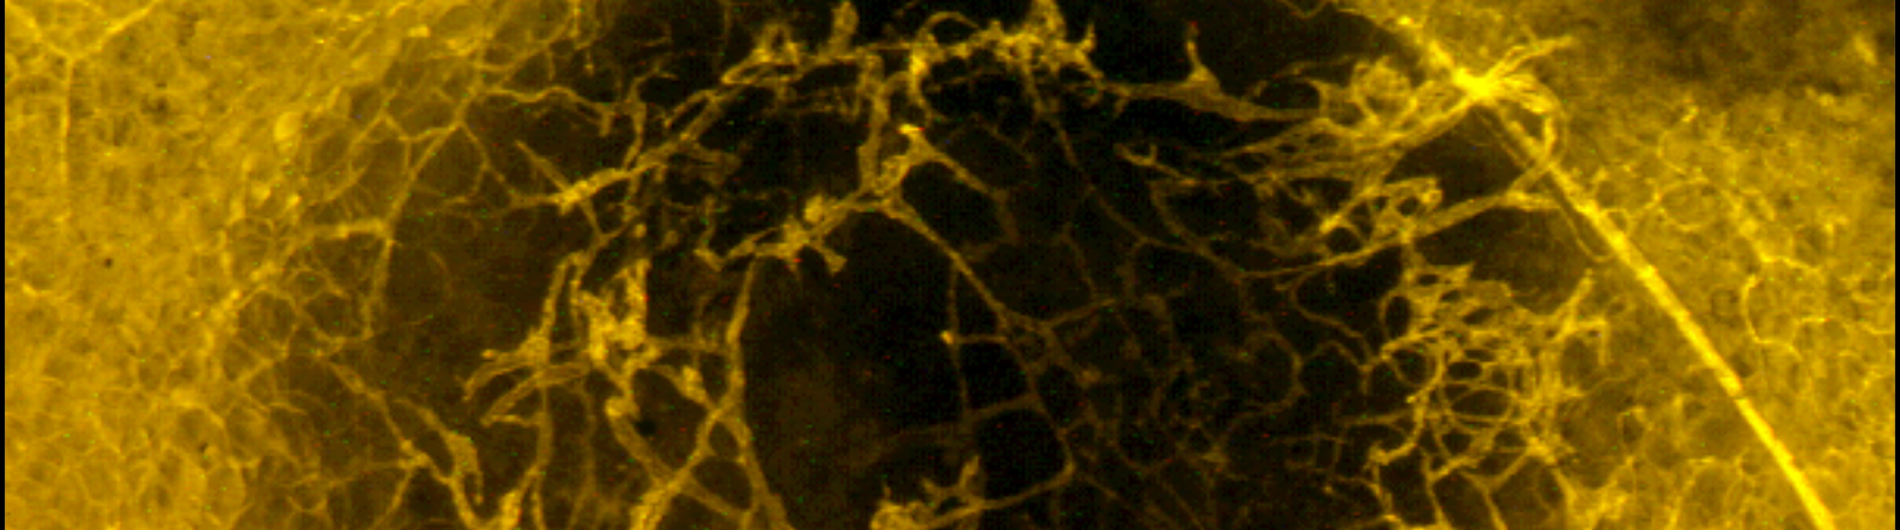

Immune cells (orange) and blood vessels (green) inside of the tumor

The immune system frequently protects us by destroying invading microorganisms such as viruses and bacteria, but is often ineffective in recognizing and combating cancer. Interestingly, immune cells are very capable of finding and killing cancerous cells, but tumor cells are unique in that they can transform immune cells to elicit tumor-promoting functions and ultimately diminish the response to cancer. The Gerber laboratory focuses on reversing this process and instead “re-activates” these immune cells to attack and eradicate the tumor. This is accomplished by a new line of cancer treatment called immunotherapy (enhancing the body’s own immune system to fight cancer), which has resulted in remarkable anti-tumor responses. Immunotherapy stands to redefine how clinicians treat tumors and may hold the key to eliminating cancer.

Tumor Microenvironment

A major obstacle blocking the way for effective cancer therapy is the tumor microenvironment. Within the tumor consists a multitude of various components ranging from cancer cells, fibroblasts, blood vessels, immune cells, nerves, bacteria, etc. Cancerous cells “program” the components of the tumor microenvironment to promote the growth of the malignancy through the production and interaction of a very complex milieu of cancer-driving factors. The Gerber lab focuses on understanding the complexities of the tumor microenvironment to identify what factors promote tumor growth and, from this data, develop therapies to counteract these molecules.